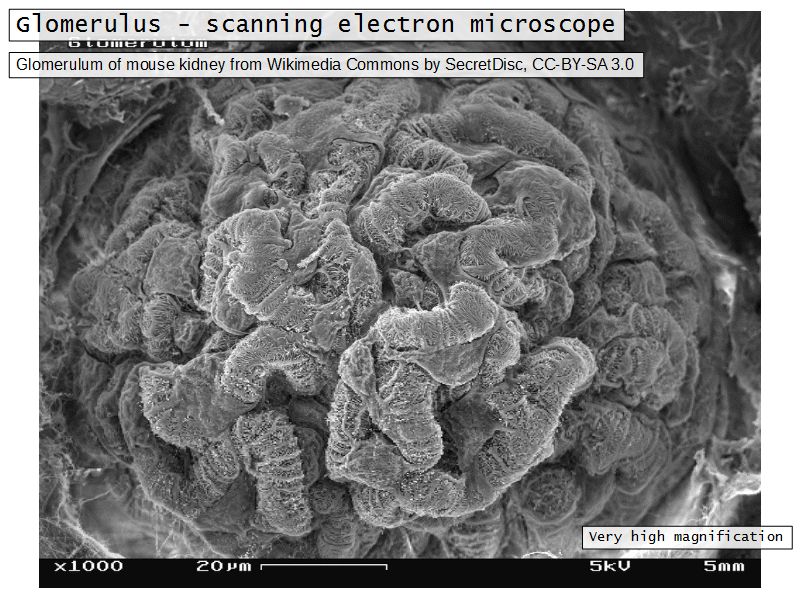

- Tuft of capillaries

- grow into

- Blind end of nephron

- Several layers of epithelium

Capillaries

- Supported by

- Mesangial cells

- Mesangial matrix

- Phagocytic

- Maintain basement membrane

- Remove macromolecular deposits

Mesangial cells

- Around capillary loops at vascular pole

- Phagocytic

- Maintain basement membrane

- Remove macromolecular deposits